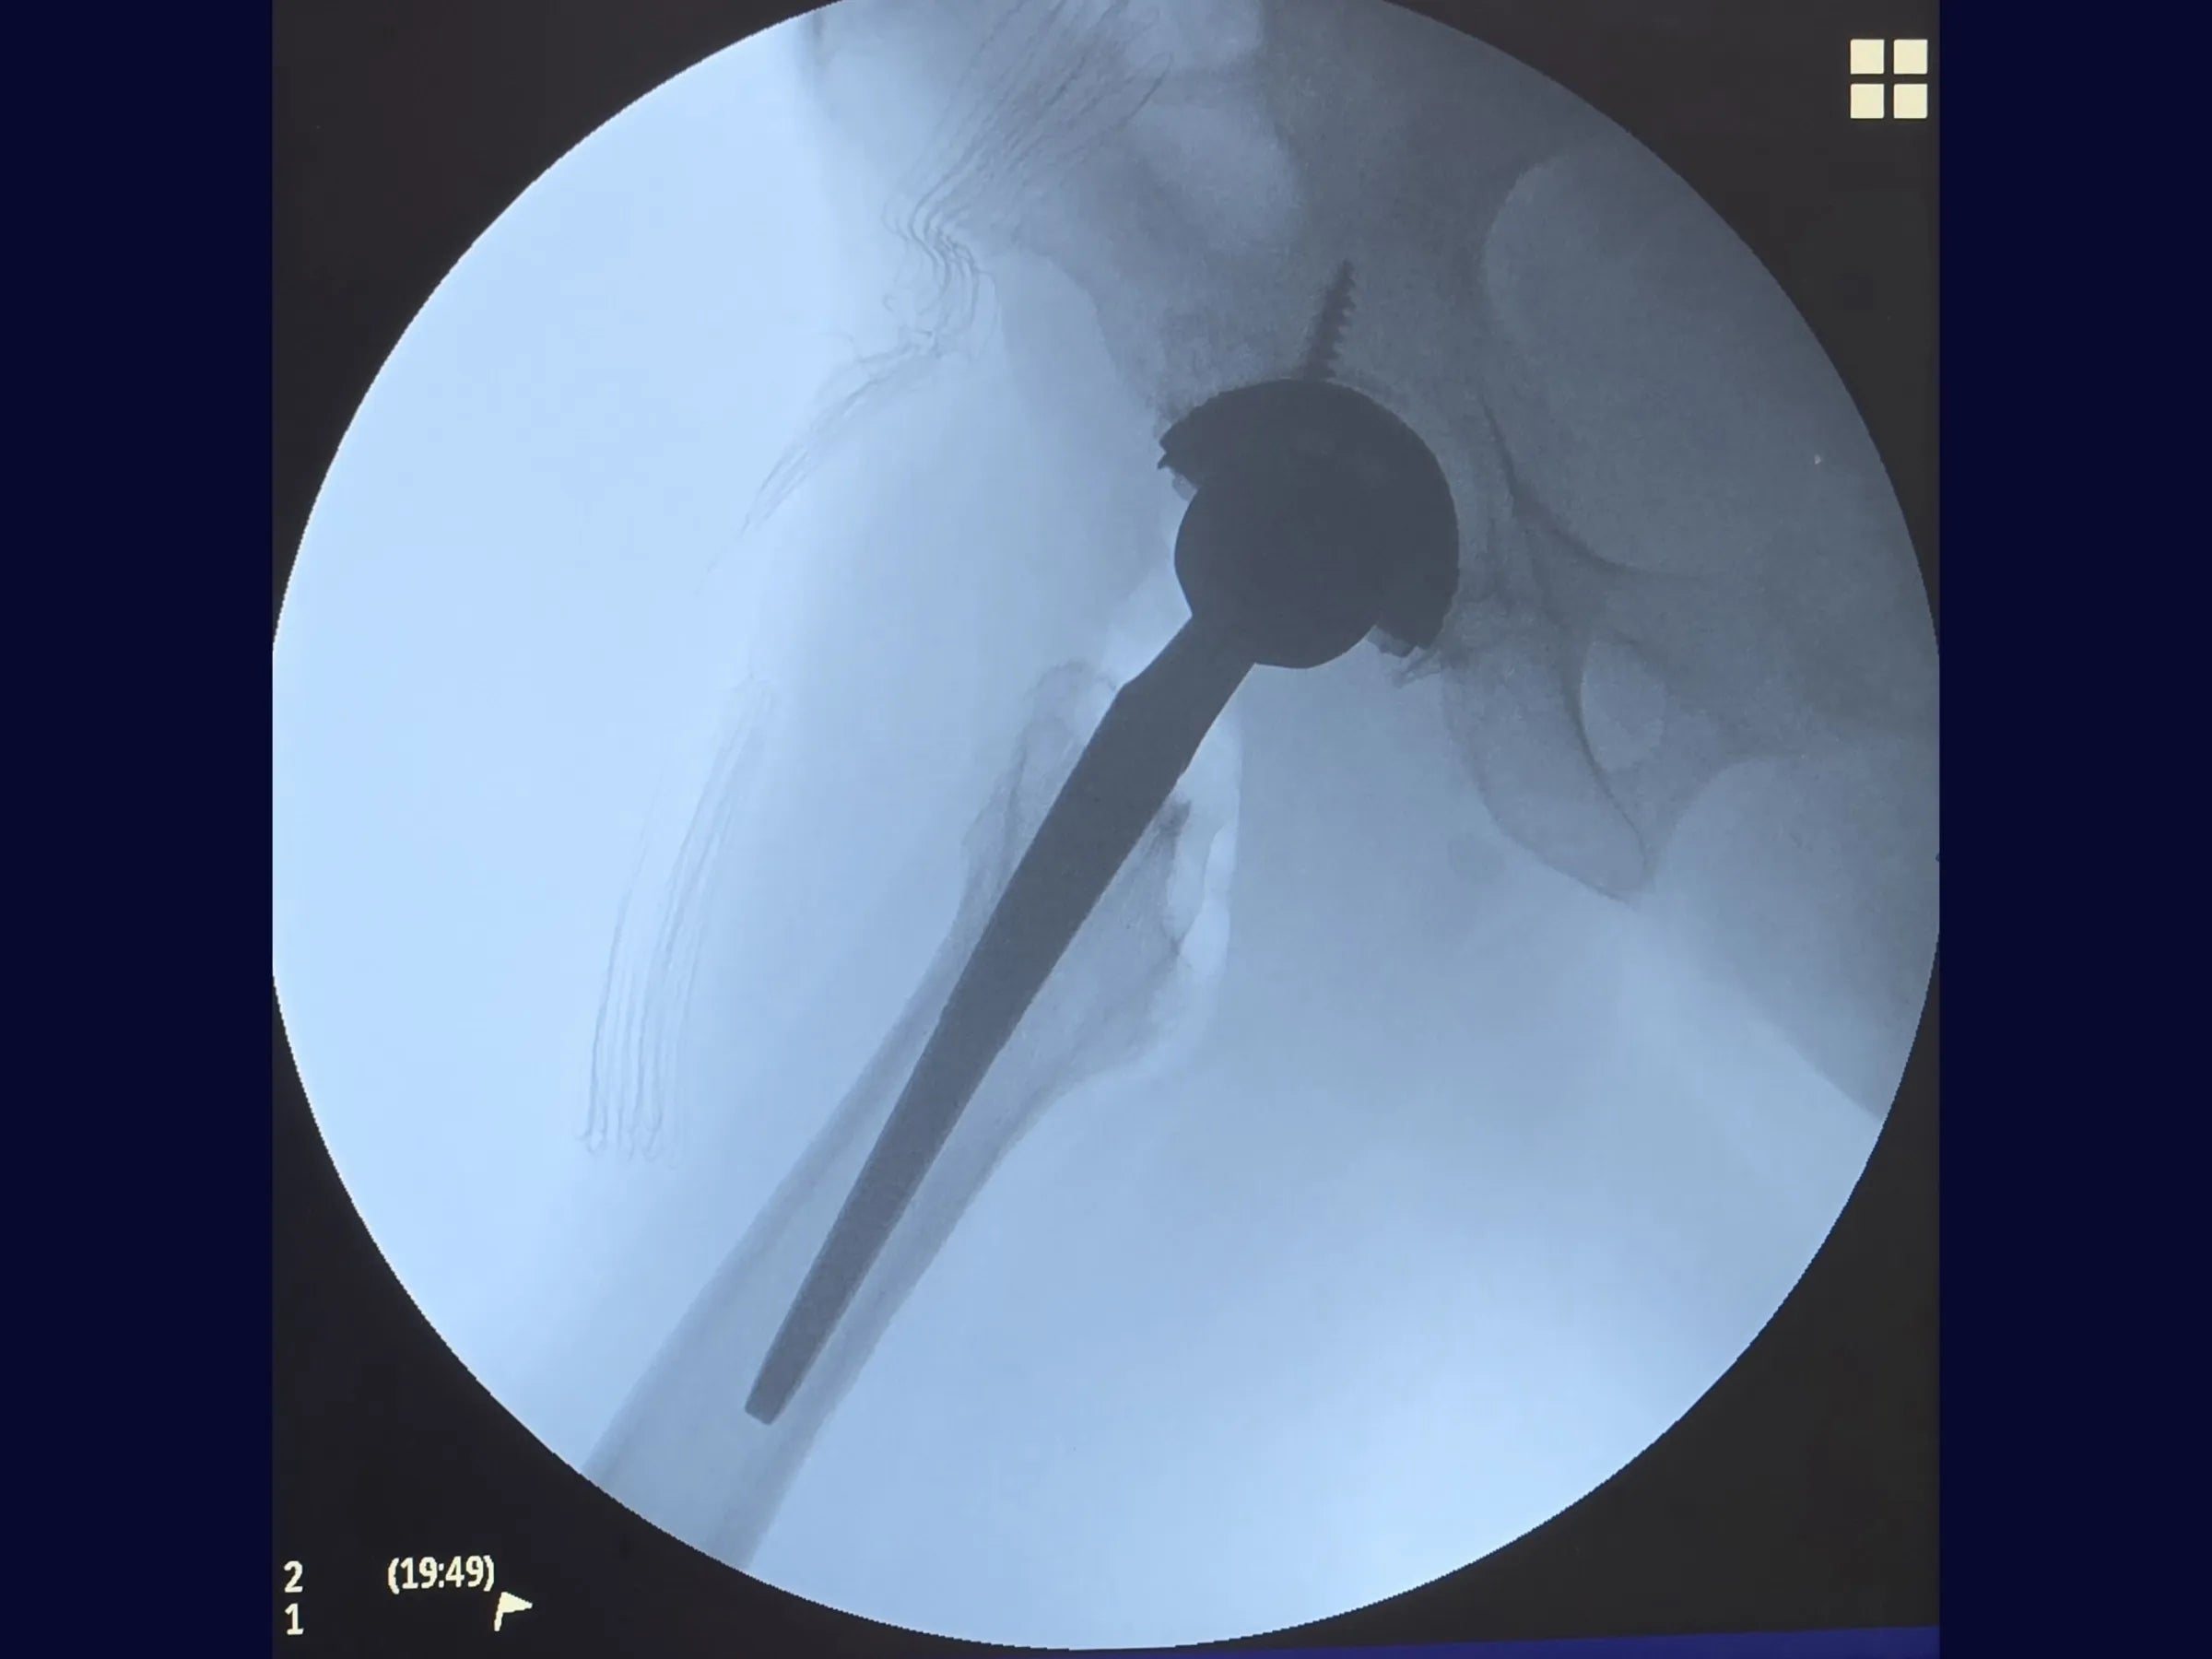

• Preparação femoral com haste não cimentada e progressão guiada por acústica;

- Sequência femoral reprodutível com critério acústico de "aderência cortical" para padronizar a progressão das fresas e implantação da haste;

- Protocolo de validação dinâmica com testes em flexão >90° e rotação interna, ajuste de tensão tecidual e verificação de comprimento antes da redução definitiva;

PDF Técnico Completo: inclui raio X, posicionamento do paciente, marcos anatômicos, instrumentais, critérios de estabilidade, algoritmos de decisão e cuidados pós-operatórios.